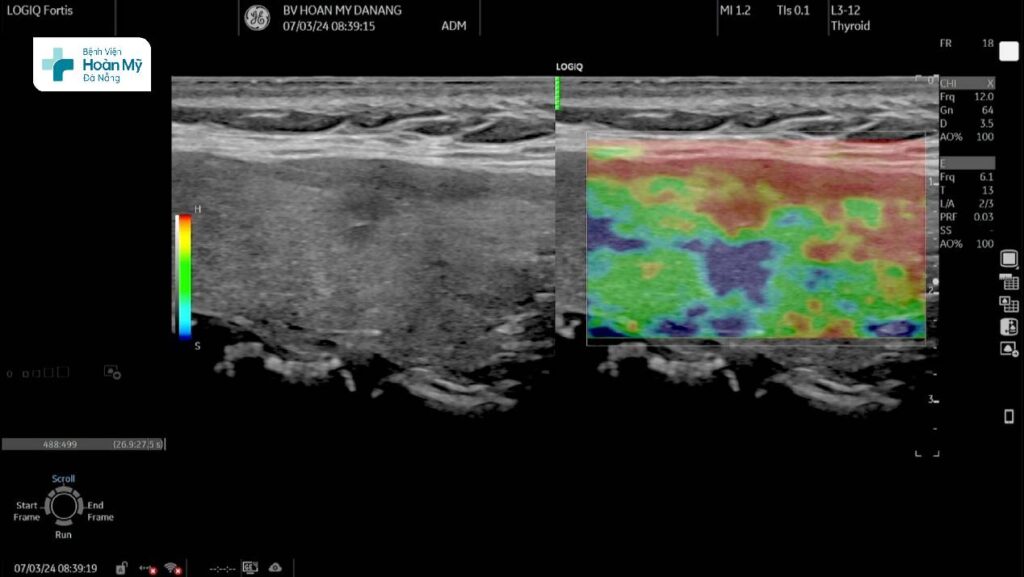

Siêu âm chẩn đoán u ác tính tuyến giáp trên máy siêu âm cao cấp LOGIQ Fortis thế hệ mới

Siêu âm B mode phát hiện nhân mặt trước thùy phải, giảm âm, trục đứng, bờ không đều, dính và lan nhẹ ra khỏi vỏ bao mặt trước, được xếp nhóm TIRADS 5. Trên siêu âm đàn hồi sức căng (strain elastography) thấy nhân cứng, xếp loại Rago Elasticity Score 5, giúp củng cố thêm độ tin cậy về khả năng ác tính của tổn thương.